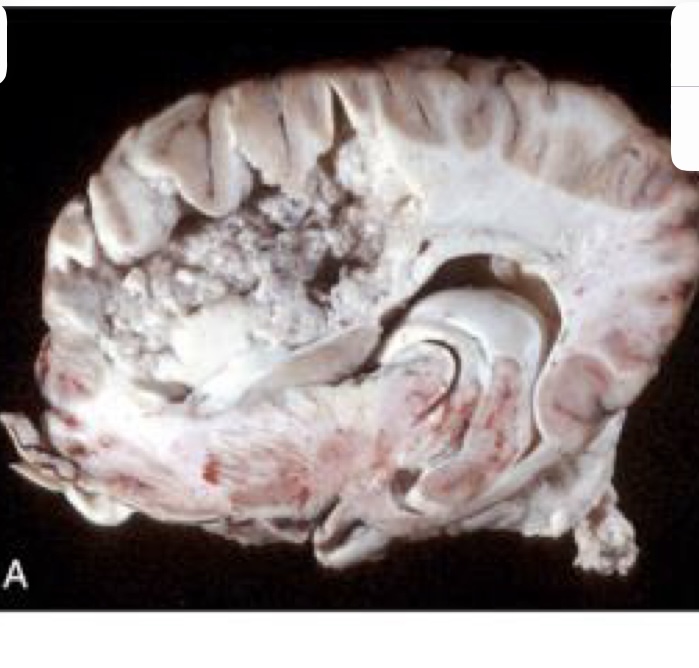

what is this?

metastatic hemangiosarcoma → prominent hematogenous metastases, which appear as black nodules of various sizes distributed throughout the brain

in an unfixed specimen, what color would the nodules of metastatic hemangiosarcoma be?

red to dark red